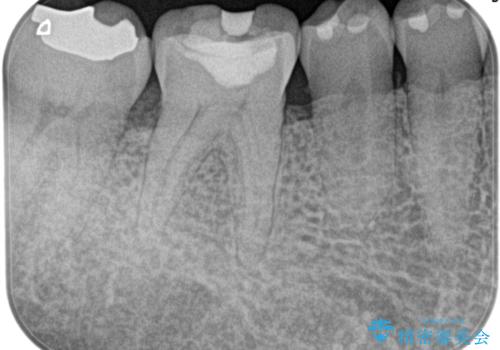

[銀歯の下の虫歯 ] 根管治療を伴う虫歯治療

![[銀歯の下の虫歯 ] 根管治療を伴う虫歯治療の症例 治療前](https://seimitsushinbi.jp/wp/wp-content/uploads/2020/05/89abd4c7a23874a1d4cee7f019e38bac-500x350.jpg?v=1590579075)